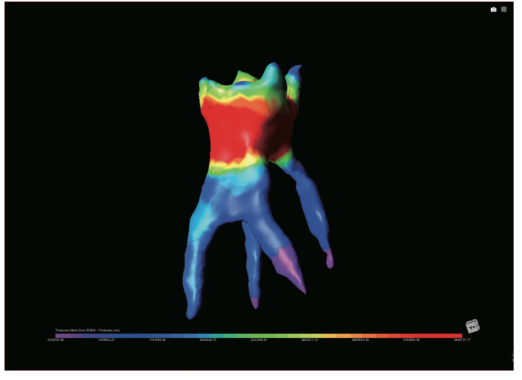

第2部分深度剖析案例,涉及口腔医学、临床医学、材料学、工学等多个学科的交叉内容,是本书的重头戏。

通过 6 个真实的医学案例,展现人工智能技术在医学图像领域的应用,从医工交叉的角度出发,深入探讨了医学图像问题处理方法,旨在让读者了解如何将人工智能技术切实落地于医学图像学中,帮助相关从业者减少重复性工作,为医生和开发者两端搭建一座沟通的桥梁,进一步推广新技术和方法在该领域的应用。

图:书中介绍界面和展示编程效果的内容

另外,书中的六个案例均源自临床,囊括了口腔、心血管、肺部、肾脏等不同科室,作者对此进行了详细的剖析,每个案例都套用书中的流程模板展开,包括图像导入、图像标注、训练模型、数据增强、图像匹配等流程,在实例中巩固对流程的掌握,在运用流程中增加对实例的理解,既有实践参考意义,也更有助于读者快速上手。